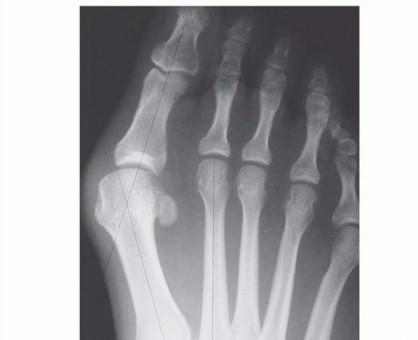

DEFINITION Freiberg infraction is an osteochondrosis of a lesser metatarsal head, most commonly involving the…